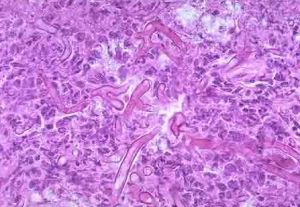

婦科檢查白帶呈白色稠厚豆腐渣樣;陰道黏膜紅腫,嚴重的形成淺潰瘍少許陰道。分泌物放於10%KOH玻片上,在顯微鏡下找到菌絲。若有症狀而多次鏡檢為陰性,可用培養法進行培養。

3.陰道分泌物中找到白色念珠菌。可取少許陰道分泌物,放於10%KOH或生理鹽水玻片上,混勻後在顯微鏡下找到菌絲,即可確診。用10%KOH可溶解其他細胞成分,檢出率陽性率為70%~80%。若有症狀而多次鏡檢為陰性,可用培養法進行培養確診。